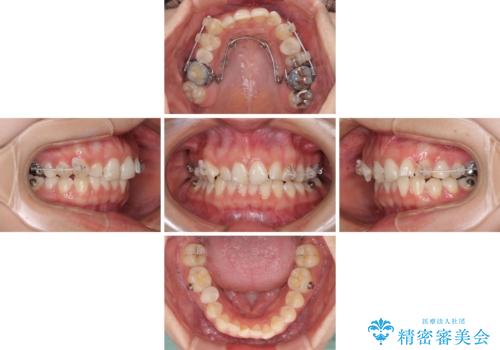

インビザラインでの矯正治療を希望されていましたが、奥歯の咬み合わせがインビザライン単独では改善困難と判断されたので、補助装置を併用することとしました。

まずは裏側の装置やワイヤー矯正を用いて歯列幅の狭い上顎を側方に拡大しつつ全体を後方に移動させ、その後インビザラインにて歯列を整えることとしました。

奥歯の咬み合わせの改善は、インビザライン単独では達成しきれないことがあるため、ワイヤー矯正などの補助装置を併用する場合があります。

インビザライン単独の場合と比べ、治療結果は大きく異なります。